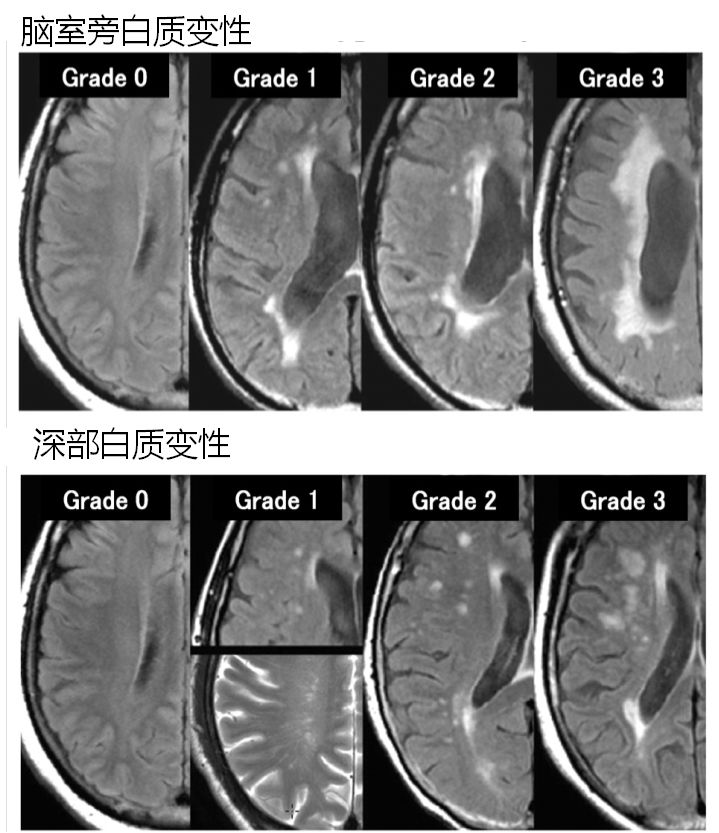

脑白质变性的学名称为“脑白质疏松症”,是指脑室周围或皮质下区CT上的弥漫性低密度带或MRI T2加权像上的弥漫性高信号区。根据分布不同主要将其分为脑室旁白质变性和深部白质变性(图像表现及分级如下图)。